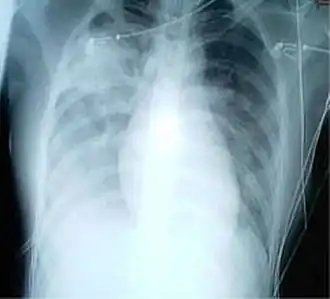

| Radiografia ao tórax em que se observa aumento de opacidade em ambos os pulmões, indicativo de pneumonia, em paciente com SARS | |